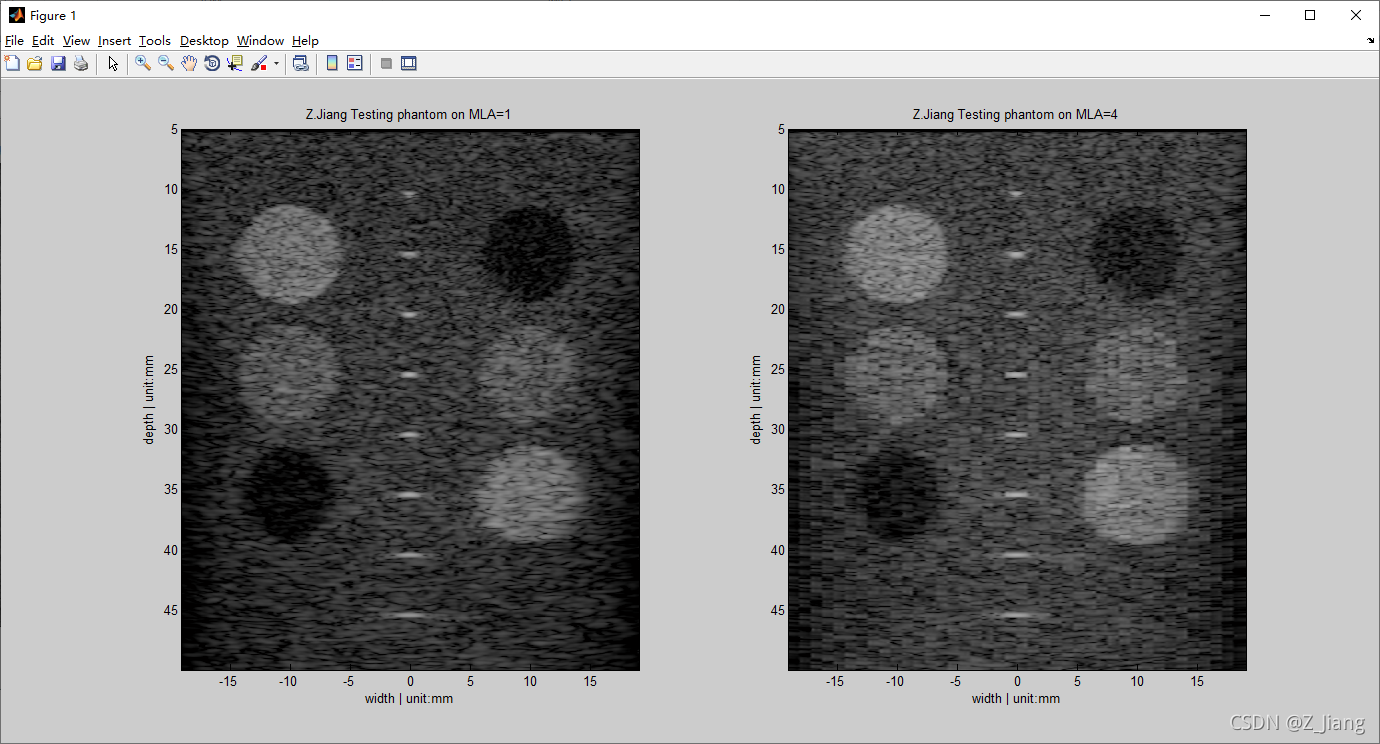

只有靶点,不方便我们系统对比MLA的实际影响,我做一个完整的体模比较,有靶点,组织,及对比分辨率靶球,如下图所示

左图:常规体模 Tx=160,MLA=1, Rx=160 右图:常规体模 Tx=40,MLA=4, Rx=160

从这个对比,大家就很好理解为什么多MLA的图像下降叫做block artifact,非常形象。